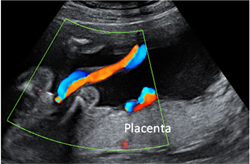

Aunque te hayan podido realizar alguna antes por diversas razones, como ocurre en el seguimiento de los embarazos mediante técnicas de reproducción asistida, en las amenazas de aborto o simplemente porque hayas "pedido el favor", en un embarazo normal la primera ecografía que tiene valor es la que se te debe realizar entre las semanas 11 y 14, cuando tu feto mide entre 4,5 y 8,4 centímetros. Este es el momento adecuado para calcular el tiempo de embarazo y para poder medir adecuadamente la translucencia nucal (TN) (que también oirás llamar de forma incorrecta pliegue nucal). Una duda frecuente es si esta ecografía se hace por vía vaginal o abdominal. Si bien es cierto que por vía vaginal "se ve mejor", también tiene sus inconvenientes como la incomodidad que supone para la paciente y las limitaciones que tiene para conseguir algunos planos.

Con los ecógrafos actuales esta exploración se podría realizar en la mayoría de las mujeres por vía abdominal y algunos preferimos realizar toda la exploración por esta vía ya que permite más versatilidad a la hora de conseguir los planos adecuados para la medición de la TN. Otros ecografistas siguen prefiriendo la vía vaginal y otros combinan ambas vías.